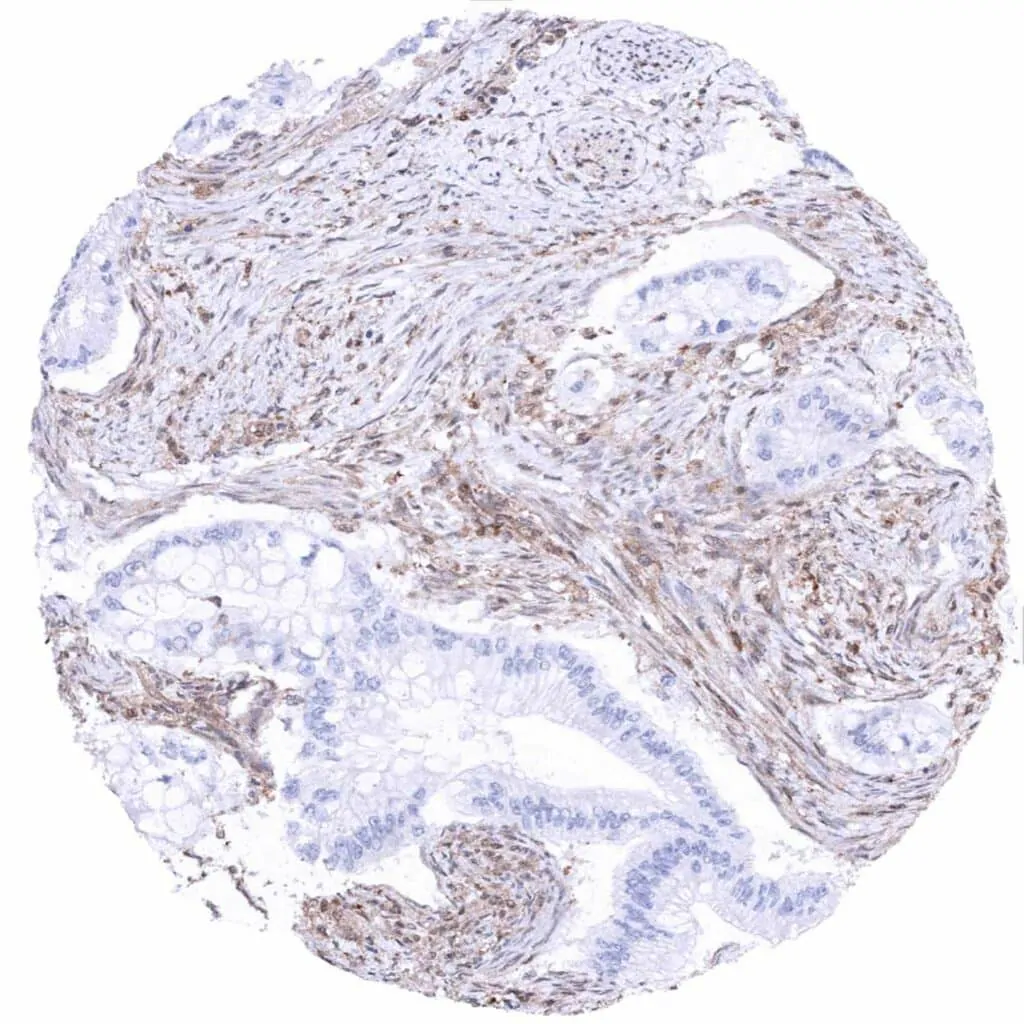

Colon – Colorectal adenocarcinoma with complete absence of MTAP staining in tumor cells. Intense MTAP staining of inflammatory and stromal cells